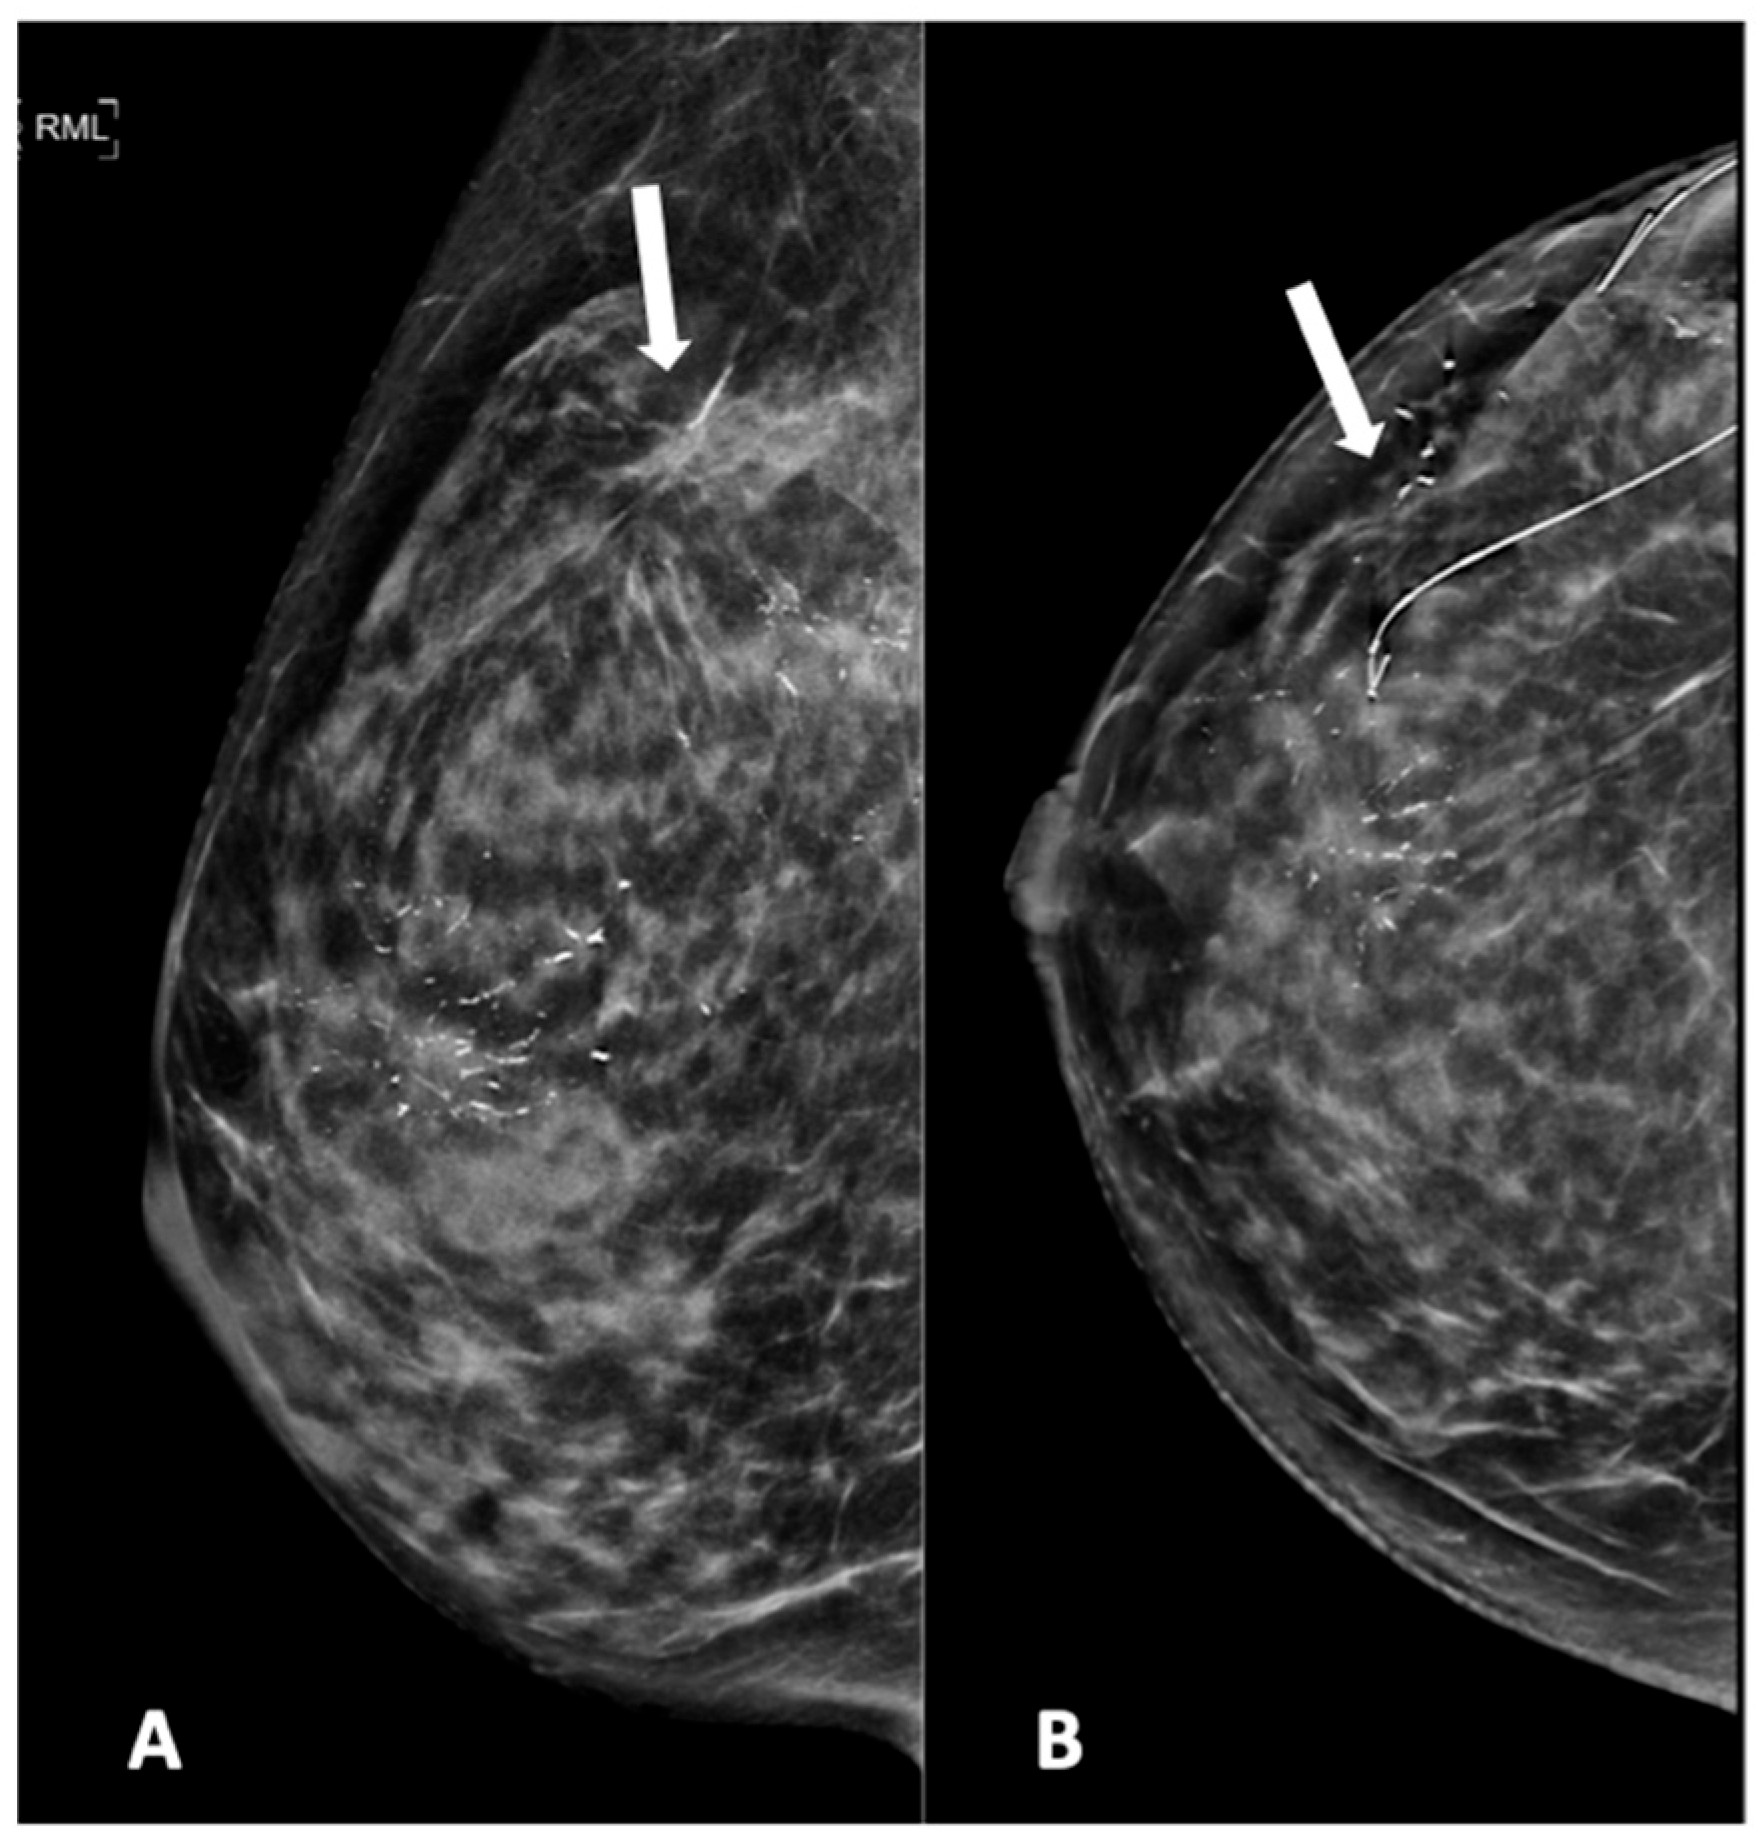

Figure 5.

Mammogram study of a right breast in (A) MLO view and (B) CC view, showing branching pleomorphic calcifications in a segmental distribution in the upper outer-to-mid quadrant, reported as a BI-RADS 4C lesion. A stereotactic-guided hook-wire insertion was performed (hook-wire in CC view), and an HPE of the wide local excision showed invasive carcinoma. We noted an architectural distortion in the upper outer quadrant (arrow) from a previous surgery.